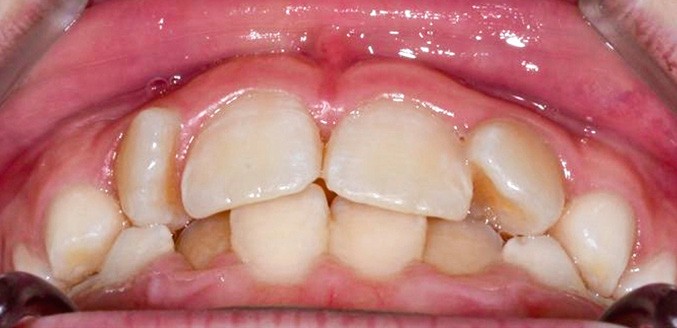

La patiente consulte à l’âge de 9 ans pour la malposition de ses incisives latérales maxillaires. Elle présente une occlusion de Classe I bilatérale sur un schéma normodivergent avec une dysharmonie dento-maxillaire en denture mixte. À l’arcade maxillaire, elle présente une endoalvéolie avec rotations mésiopalatines de 16 et 26.

Sur la radiographie panoramique, on observe une transposition des canines maxillaires en place d’incisives latérales, au contact des racines de 11 et 21.